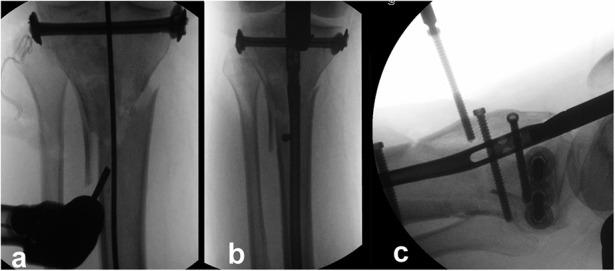

Bicondylar tibial plateau fractures have been treated with either plating or external fixation techniques, with conflicting results. A recently introduced technique involving the combined use of intramedullary nailing via a suprapatellar approach and condylar bolts could represent a new pathway toward better treatment of this severe injury.

The present report describes a retrospective and prospective study of all 17 patients (age range, 25 to 75 years) who were admitted under the author's care for the treatment of a closed, bicondylar tibial plateau fracture between 2013 and 2015. All patients consented to undergo fixation of the fracture with intramedullary nailing through a suprapatellar approach and with use of condylar bolts. The reconstructed articular surface was supported with freeze-dried allograft that had been previously soaked in concentrated bone marrow. The patients were followed at regular intervals, and the results were assessed with the Knee injury and Osteoarthritis Outcome Score (KOOS).

双髁胫骨平台骨折的治疗方法有钢板固定或外固定技术,但结果存在争议。最近引入的一种技术,即通过髌上入路联合使用髓内钉和髁螺栓,可能为更好地治疗这种严重损伤开辟一条新途径。

本报告描述了一项回顾性和前瞻性研究,研究对象为2013年至2015年间在作者治疗下因闭合性双髁胫骨平台骨折入院的所有17例患者(年龄范围25至75岁)。所有患者均同意采用髌上入路髓内钉固定并使用髁螺栓固定骨折。用预先浸泡在浓缩骨髓中的冻干同种异体骨支撑重建的关节面。定期对患者进行随访,并采用膝关节损伤和骨关节炎疗效评分(KOOS)评估结果。